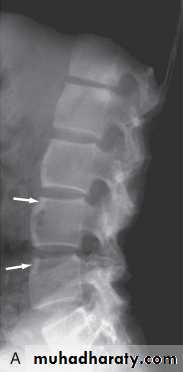

In established AS, radiographs of the sacroiliac joint show irregularity and loss of cortical margins, widening of the joint space and subsequently sclerosis, joint space narrowing and fusion.Lateral thoracolumbar spine Xrays may show anterior ‘squaring’ of vertebrae due to erosion and sclerosis of the anterior corners and periostitis of the waist.

Bridging syndesmophytes may also be seen. These are areas of calcification that follow the outermost fibres of the annulus

Investigations

In advanced disease, ossification of the anterior longitudinal ligament and facet joint fusion may also be visible. The combination of these features may result in the typical ‘bamboo’ spine.Erosive changes may be seen in the symphysis pubis, the ischial tuberosities and peripheral joints.